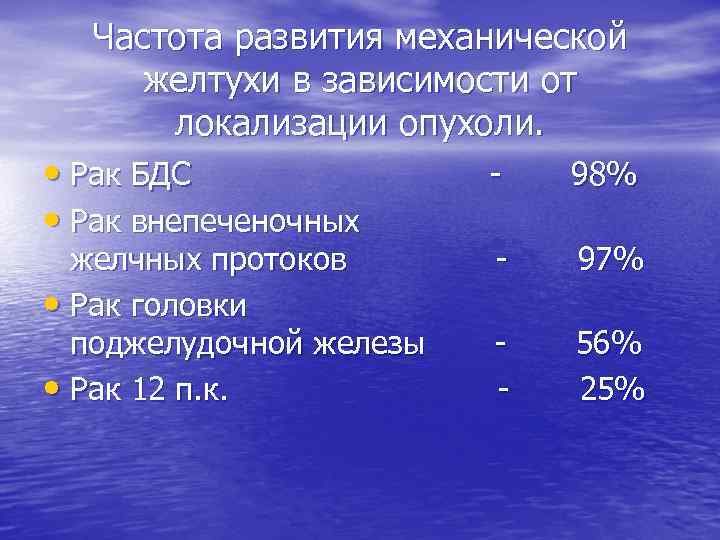

Частота развития механической желтухи в зависимости от локализации опухоли. • Рак БДС • Рак внепеченочных желчных протоков • Рак головки поджелудочной железы • Рак 12 п. к. - 98% - 97% - 56% 25%